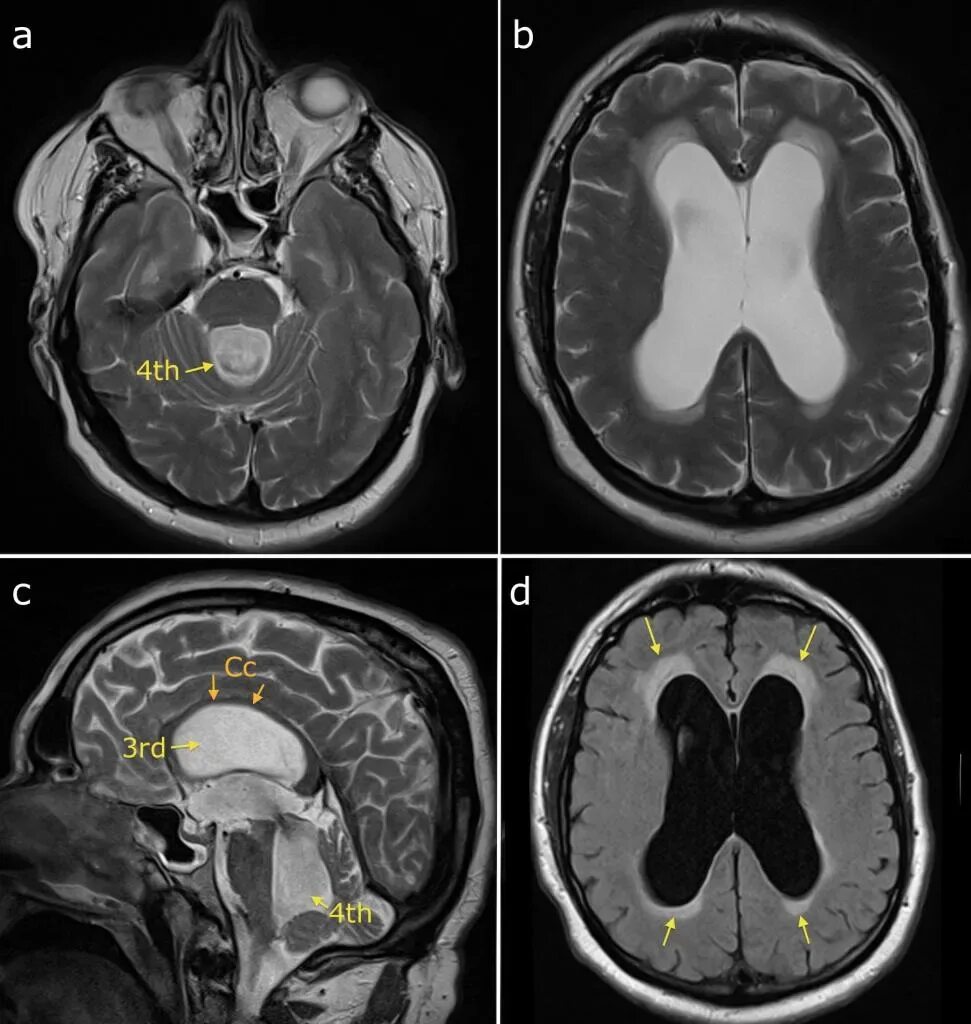

Умеренная гидроцефалия головного мозга у взрослых